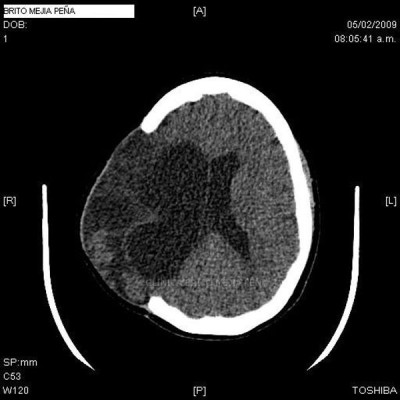

Cabeza y Cuello 2

Envíado por BMP Imágenes Diagnósticas

BMP Imágenes Diagnósticas